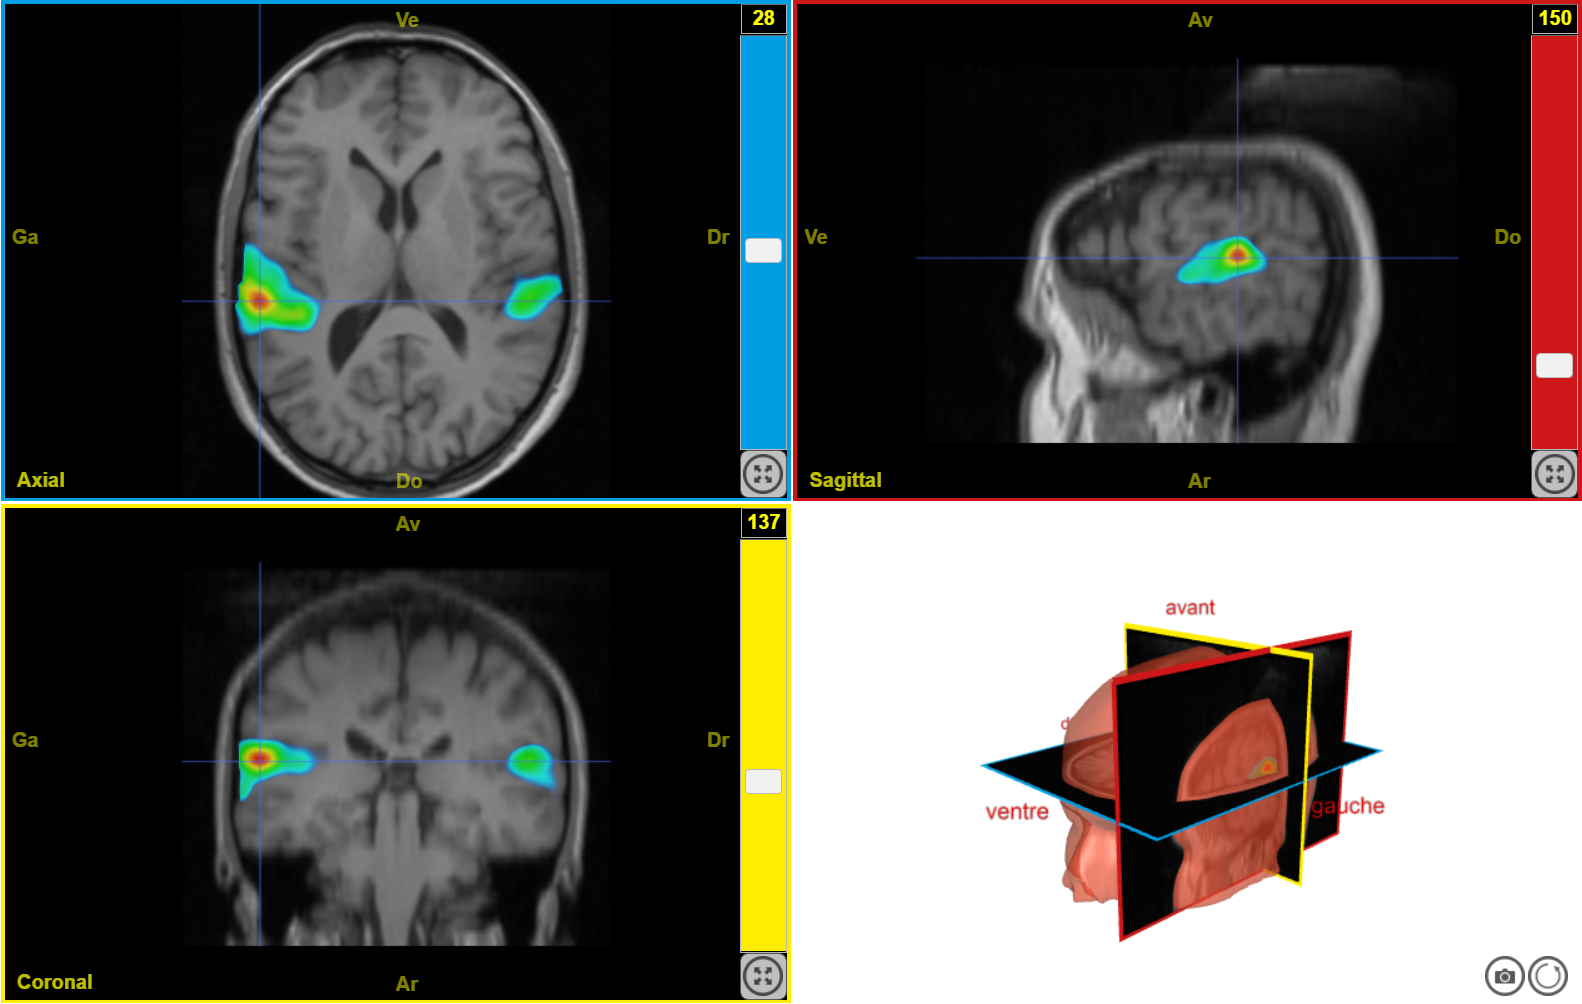

IRMf syllabes seuil 50